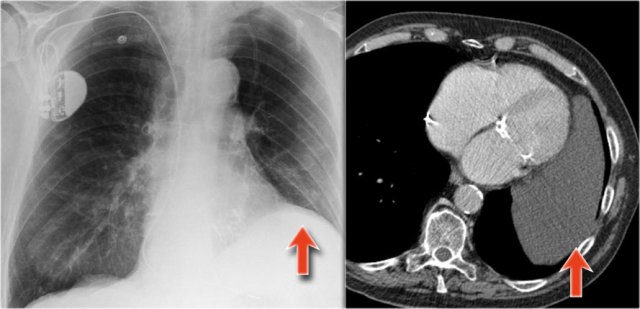

Hidden areas (3)

Here a pneumonia which was hidden in the right lower lobe mainly below the level of the dome of the diaphragm (yellow arrow).

Notice the increase in density on the lateral film in the lower vertebral region.

You may have to enlarge the image to get a better view.